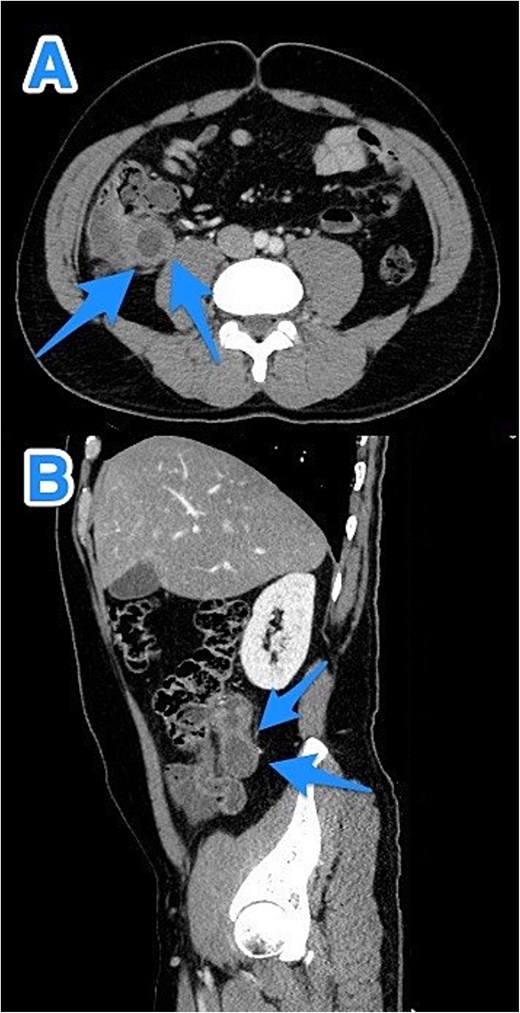

A 47-year-old male patient, with a documented history of diabetes mellitus but no previous surgical interventions, presented with right lower quadrant (RLQ) abdominal pain, which was associated with recurrent vomiting episodes (four times) within the preceding 24 h. The pain did not radiate and was not aggravated by any specific factors. The patient denied fever, urinary symptoms, and changes in bowel habits. On physical examination, he appeared well, with mild pain but no distress. Abdominal examination revealed minimal tenderness and rebound tenderness in the RLQ, but the abdomen was otherwise soft and lax, with no evidence of guarding, rigidity, or fullness. The patient’s laboratory profile was within normal ranges. Abdominal computed tomography (CT) with contrast revealed a dilated, fluid-filled appendix with a maximum diameter of 2.2 cm and tiny peripheral calcifications. There was no surrounding fat stranding or free fluid. The rest of the bowel loops were grossly unremarkable (Fig. 1). A diagnosis of appendicular mucocele was made, and the patient underwent an open appendectomy. The patient’s postoperative course remained clinically uneventful. Gross findings of the appendectomy specimen measured 6 × 2.5 × 2 cm, with a smooth outer surface and no identified perforation. Pathology examination revealed LAMN, confined to the appendix. The sections showed flat mucinous epithelium originating from the lumen, and there was no evidence of extra-appendiceal mucinous extension. The margin was negative for mucinous neoplasm (Fig. 2). A referral to the Colorectal Surgery Clinic was arranged to ensure a thorough evaluation and appropriate follow-up.

CT abdomen and pelvis with contrast—Axial (A) and sagittal (B) views highlighting a dilated, fluid-filled appendix with a maximum diameter of 2.2 cm and small peripheral calcifications (arrows).